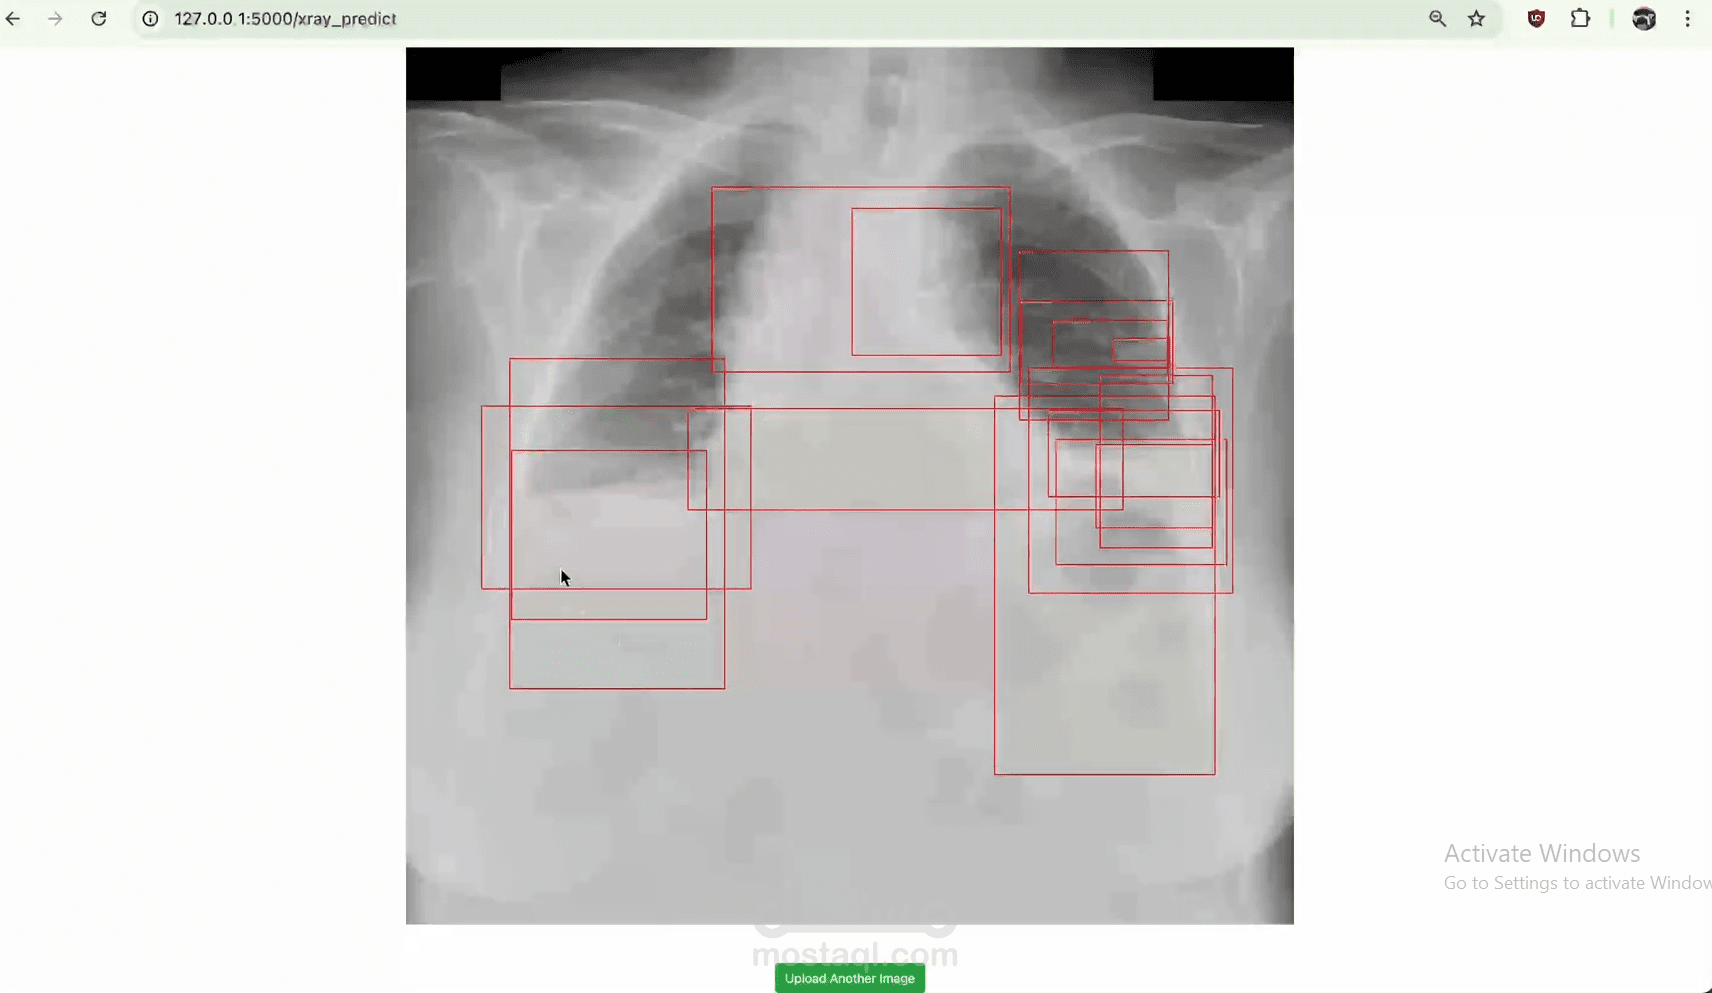

المشروع ده عبارة عن نظام تفاعلي للتنبؤ بأمراض الرئة باستخدام صور طبية مثل الأشعة السينية x-ray، أشعة الرنين المغناطيسي MRI، وأشعة المقطعية CT. النظام بيستخدم تقنيات الذكاء الاصطناعي لتحليل الصور الطبية بدقة وتقديم تشخيص سريع

النظام نجح في تقديم منصة دقيقة لتحليل وتشخيص أمراض الرئة. استخدم تقنيات التعلم العميق لتحليل صور الأشعة السينية والرنين المغناطيسي بدقة عالية. ده ساعد في تحسين سرعة التشخيص وتقليل الأخطاء البشرية